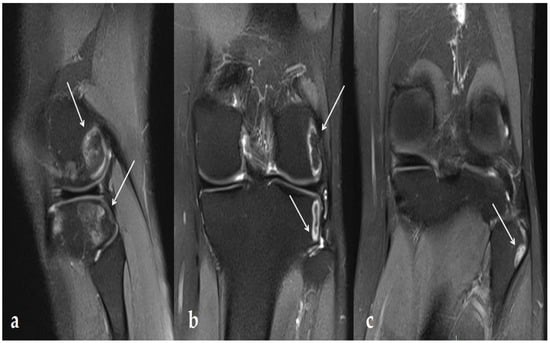

- Yeh, L.-R.; Chen, C.K.H.; Tsai, M.-Y.; Teng, H.-C.; Lin, K.-L. Focal Bone Abnormality as a Complication of Ultrasound Diathermy: A Report of Eight Cases. Radiology 2011, 260, 192–198. [Google Scholar] [CrossRef]

- Kim, S.J.J.; Kang, Y.; Kim, D.H.; Lim, J.Y.; Park, J.H.; Oh, J.H. Focal Bone Marrow Lesions: A Complication of Ultrasound Diathermy. Clin. Shoulder Elb. 2019, 22, 40–45. [Google Scholar] [CrossRef]